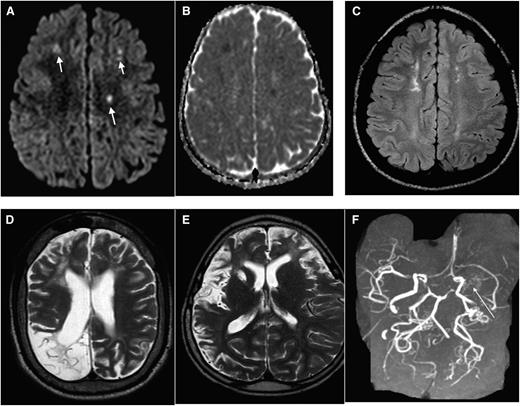

Due primarily to compromised cerebral hemodynamics, many cerebral infarcts are located in the border zone regions of the brain: the area between the cortical territories of the anterior cerebral artery, middle cerebral artery (MCA), and posterior cerebral artery; and in the periventricular white matter between the deep and the superficial arterial systems of the MCA, or between the superficial systems of the MCA and anterior cerebral artery, referred to as the internal border-zone region.9 Figure 1A-F shows a spectrum of MRI abnormalities ranging from cerebral infarcts, encephalomalcia and vasculopathy in individuals with SCD.

MRI in SCD: spectrum of abnormality in SCD as illustrated by different imaging examples. Axial DWI (A) and apparent diffusion coefficient (ADC) (B) map of the brain demonstrating multiple foci of restricted diffusion along bifrontal regions (corresponding to the short arrows in A), along the internal watershed zone most consistent with acute strokes. (C) Axial fluid attenuation inversion recovery (FLAIR) image in a different patient with SCD demonstrate areas of old (silent) infarctions in a similar internal watershed distribution. (D) Axial T2 image shows a large area of right occipital cystic encephalomalacia resulting from prior infarction. (E) Axial T2 image from another patient shows diffuse volume loss, sulcal prominence, and an old right basal ganglia infarct from sickle cell-associated vasculopathy. (F) Maximum intensity projection image from the MRA shows nonvisualization of the left MCA with multiple collateral in the left lenticulostriate distribution (long arrow), consistent with moyamoya collaterals.